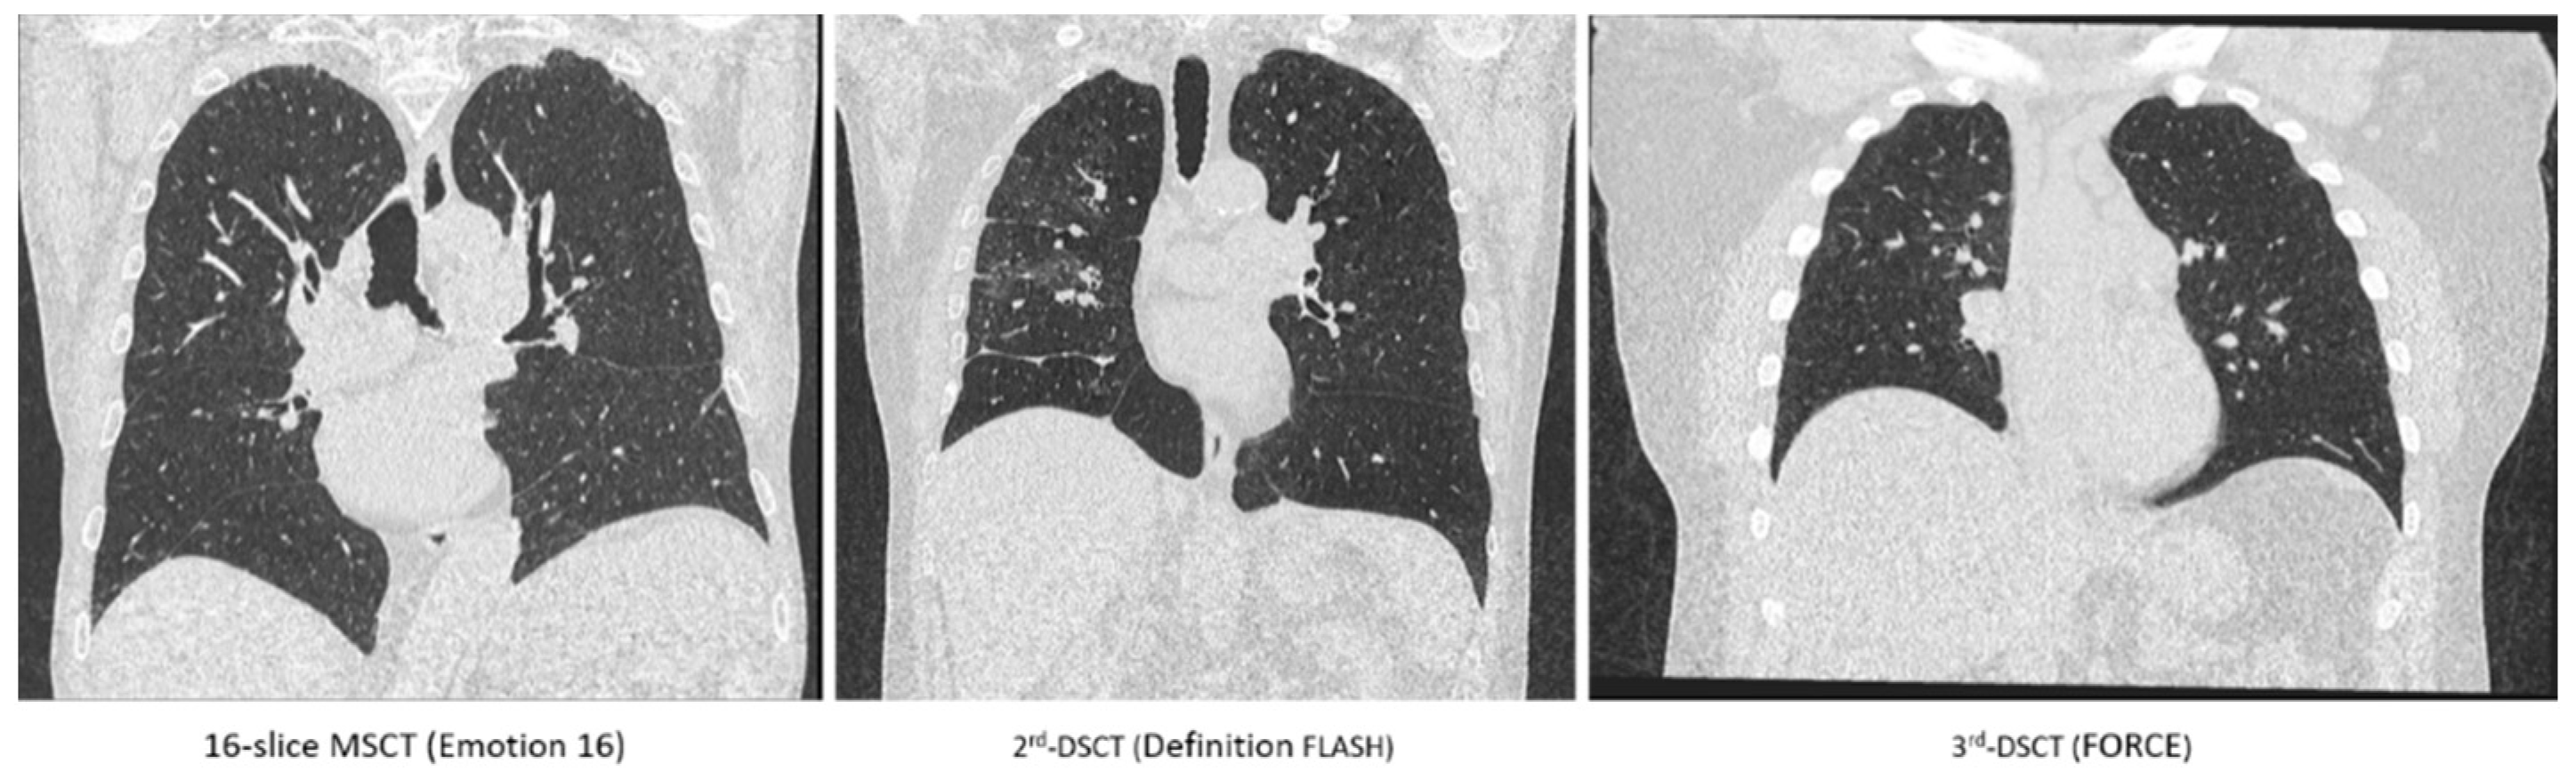

| Emotion 16 | Definition FLASH | FORCE | |

|---|---|---|---|

| Tin filter | No | No | Yes |

| Automated tube voltage modulation | Yes | Yes | Yes |

| Tube voltage [kVp] | 130 | 120 | 120 |

| Reference current [mAs] | 50 | 50 | 96 |

| Pitch | 0.8 | 0.6 | 1.2 |

| Rotation time [s] | 0.6 | 0.3 | 0.25 |

| Detector collimation [mm] | 16 × 1.2 | 128 × 0.6 | 192 × 0.6 |

| Iterative reconstruction | No | Yes | Yes |

| Slice thickness [mm] | 1.5 | 1.5 | 1.5 |

| Size of reconstructed images | 512 × 512 | 512 × 512 | 512 × 512 |